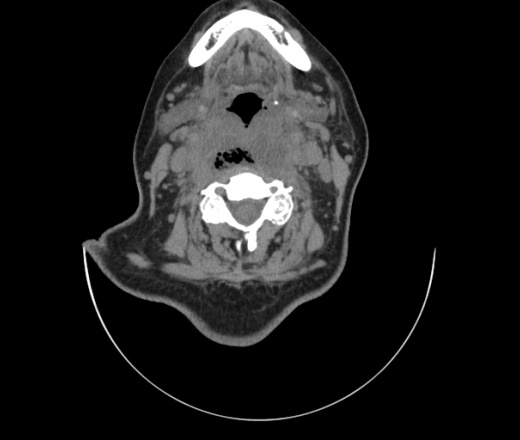

Женщина поступила в х/о спустя 4 дня после того как при употреблении карася подавилась костью.

Наличие газа в средостении на протяжении тел С2-С6 (медиастинальна эмфизема); рыбная кость на уровне тела С6.

При всем уважении, но говорить о медиастинальной эмфиземе, оценивая мягкие ткани шеи, как-то слишком резко. На мой взгляд, это ретрофарингеальное пространство.

Эвакуировали почти 100мл гноя. Но кость не смогли найти. Думаю что она даст дальнейшее ослоднение. Эндоскопически за черпалонадгортаной звязкой не смогли зайти в пищевод, все мягкие ткани отечные, просвет пищевода сдавлен. По всей видимости параэзофагеальная клетчака тоже задействована. Эмпиема, если ее можно так назвать, незнаю как правильно дошла до уровня яремной вырезки. Чем закончиться напишу. Ждем медиастинита.

Флегмона заглоточного пространства шеи, только операция, флегмоны вскрывают. Риск медиастинита.

Согласен с Вами; конечно, наличие газа в клетчатке ретрофарингеального пространства (затмение с опечаткой..). К сожалению, процесс "продвигается" к медиастиниту. Но почему никто, не отмечает наличие рыб. кости; или это для Всех очевидно?

Так вы уже отметили. Хотя ориентировал бы не скелетотопически, а на перстнечерпаловидный сустав.

Кость то мы сразу выявили, размеры где то 17*2мм, но ее так и не получается найти в этой каше